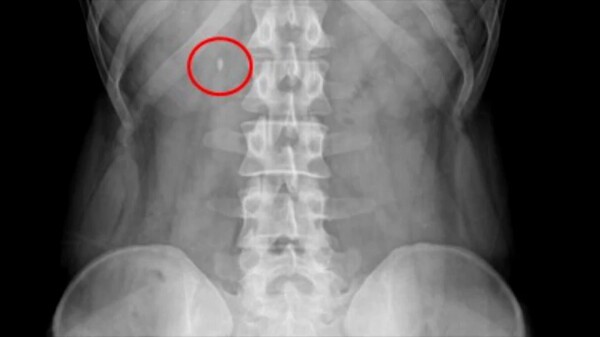

이 기술은 조영제 투여 없이 촬영한 복부 CT 영상을 인공지능 알고리즘으로 분석해 요로결석이 의심되는 부위의 유무, 크기, 위치 정보를 의료진에게 제공하는 역할을 한다.

쉽게 말해 AI가 먼저 CT 영상을 샅샅이 훑어보고 '이곳에 이만한 크기의 결석으로 의심되는 부분이 있다'고 표시해주는 것이다. 이는 방대한 영상 데이터를 빠르고 정확하게 분석해야 하는 영상의학과나 비뇨의학과 전문의의 진단 과정을 보조해 판독 정확도를 높이고 시간을 단축하는 데 기여할 것으로 기대된다.